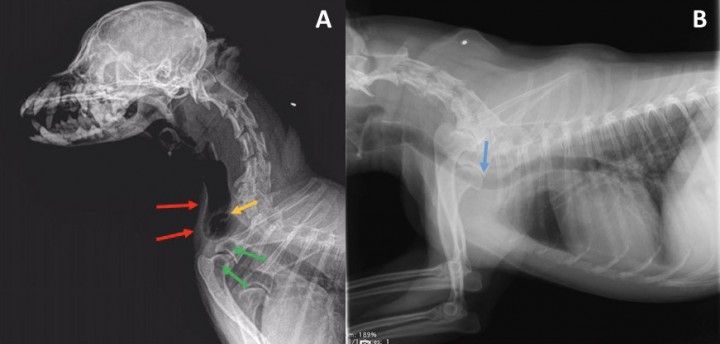

En la Fig. 3A se observa una dilatación grave de la tráquea en su porción cervical asociada a una mala alineación de la misma a la entrada del tórax (flechas rojas), visualizándose un pliegue traqueal en localización dorsal (flecha amarilla). A su vez, se aprecia un desplazamiento craneal del pulmón sobrepasando la entrada del tórax (flechas verdes).

Se visualizan cambios discales degenerativos crónicos en la región cervical caudal con espondilosis ventral grado II-III, así como reducción asociada del espacio intervertebral.

No se hallan anomalías radiográficas visibles a nivel de la cabeza ni de la región laríngea.

En la Fig. 3B se aprecia un diámetro traqueal homogéneo en todo su recorrido, tanto cervical como torácico, con una leve reducción del calibre intraluminal traqueal a la entrada del tórax, así como un desplazamiento ventral de la tráquea en esta localización (flecha azul). No se observan patologías mediastínicas/pleurales. El corazón y los grandes vasos no presentan alteraciones significativas, con ausencia de cardiomegalia y/o remodelación cardíaca. No se aprecian patrones pulmonares de interés.

<p>Comparación de las radiografías de las Figs. 1 y 2. (<strong>A</strong>) Dilatación grave de la tráquea en su porción cervical asociada a una mala alineación de la misma a la entrada del tórax (flechas rojas). Se observa el lóbulo craneal izquierdo herniado (flechas verdes), así como la torsión de la tráquea extratorácica (flecha amarilla). (<strong>B</strong>) Se aprecia una leve reducción del calibre intraluminal traqueal a la entrada del tórax, así como un desplazamiento ventral de la tráquea en esta localización (flecha azul).</p>

Comparación de las radiografías de las Figs. 1 y 2. (A) Dilatación grave de la tráquea en su porción cervical asociada a una mala alineación de la misma a la entrada del tórax (flechas rojas). Se observa el lóbulo craneal izquierdo herniado (flechas verdes), así como la torsión de la tráquea extratorácica (flecha amarilla). (B) Se aprecia una leve reducción del calibre intraluminal traqueal a la entrada del tórax, así como un desplazamiento ventral de la tráquea en esta localización (flecha azul).

Los hallazgos descritos en la Fig. 3A son compatibles con torsión de la tráquea extratorácica en asociación con una herniación pulmonar cervical adquirida.

Los hallazgos descritos en la Fig. 3B son compatibles con la presencia de una membrana dorsal redundante/superposición esofágica con desplazamiento ventral.